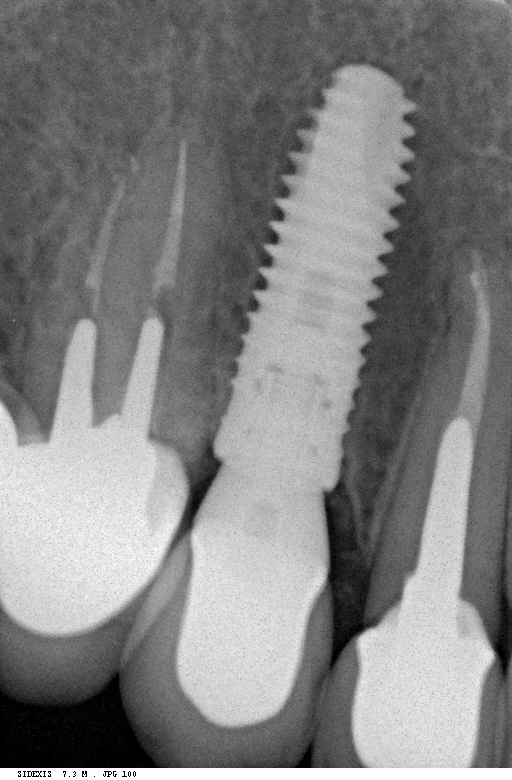

Исследование на рентгене после имплантации зубов

Раздел: Снимки-откровения